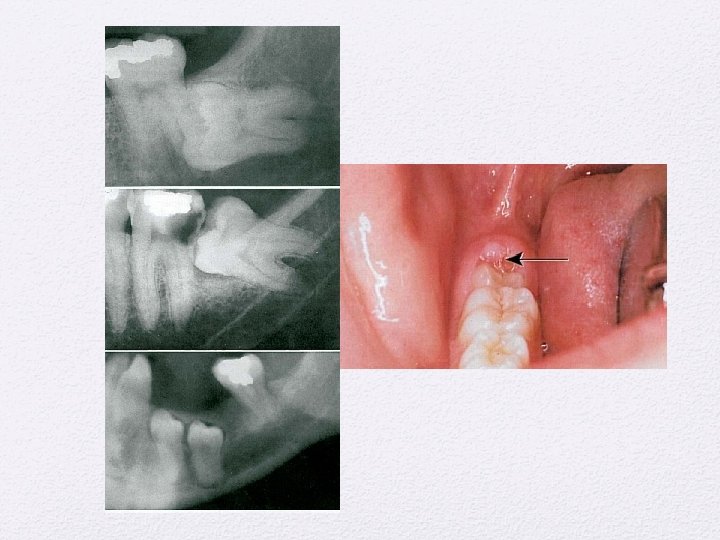

Kista Odontogenik • Kista periapikal • Kista Dentigerous • Kista erupsi • Kist Paradental • Odontogenik keratocyst • Kista lateral periodontal • Kista ginggiva • Kista dental lamina • Kista Glandular odontogenik

Lesi Periapikal • Periodontitis apikalis kronis • Granuloma periapikal • Kista periapikal • Abses periapikal